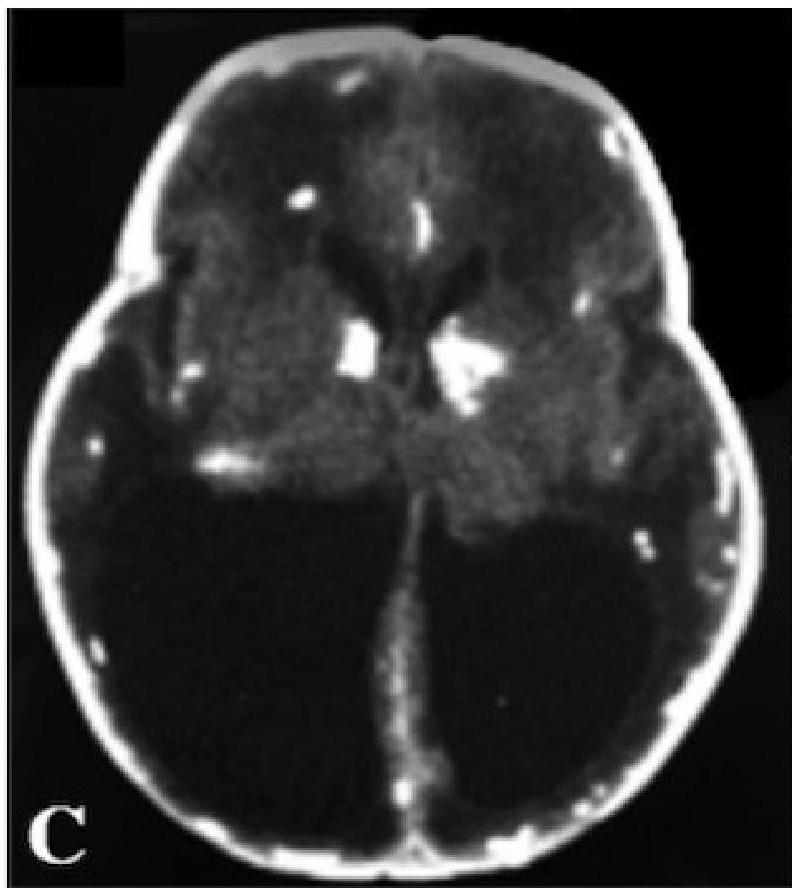

- Neurological: Microcephaly, Seizures, Intracranial calcifications (classically periventricular).

Ventriculomegaly and calcification of congenital CMV

- Imaging: Cranial ultrasound/CT → periventricular calcifications, ventriculomegaly.